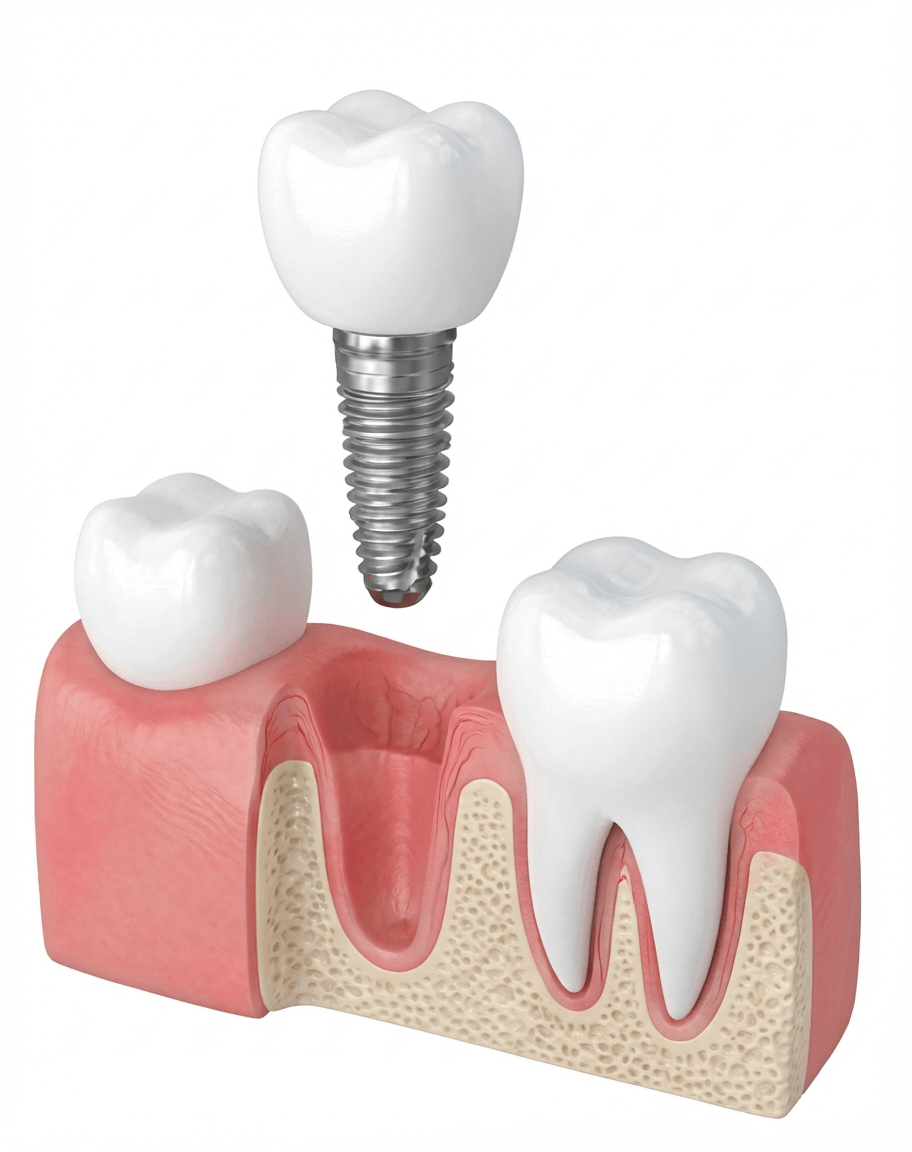

最も一般的で安全性の高い方法

一般的なインプラント治療です。痛み・腫れを最小限にしたインプラント治療を行います。

一次手術(インプラント埋入)

待機期間(2〜6ヶ月)

インプラントと骨がしっかり結合するのを待ちます。

二次手術(アバットメント装着)

インプラントに土台を取り付けます。

人工歯の製作・装着